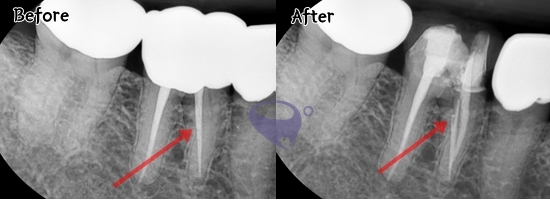

신경치료는 충치가 치수 조직까지

감염시켰을 때 진행하게 되는데요.